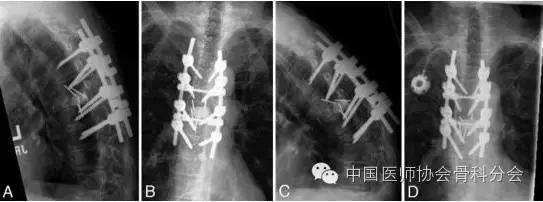

图2. 病例1.早期(A和B)和后期(C和D)的正侧位的X线片显示:胸9压缩性骨折间断性发展并伴有节段性后凸以及棒下端的向后移位